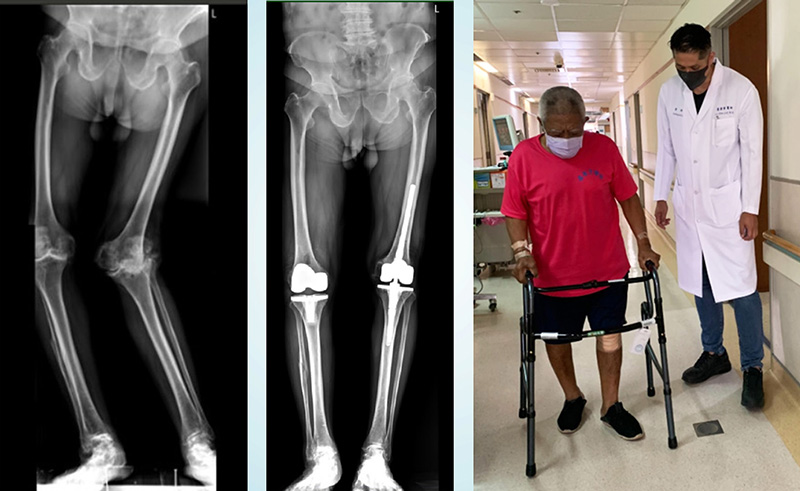

照完X光,果然印證了我的想法,非常嚴重的關節退化及骨頭侵蝕造成膝蓋嚴重外翻變形。「伯伯,您怎麼拖那麼久才來看診?」我不捨地問「您這幾年都怎麼撐過來的?沒有醫生建議你要開刀嗎?」

阿伯回家跟家人商量後,終於決定來高雄住院接受人工膝關節置換手術了。出院之後我們沛緹個管師利用line跟電話持續的關心阿伯,家屬傳來照片確認傷口的狀態、指導止痛藥物的使用、也用影片來觀察阿伯行走復健的姿勢,確認一切復原進度都如預期。科技的進步拉近了醫病的距離。

手術後我到衛生所看他,他跟我說這次的選擇真的是太棒了,不僅解決了困擾他20年的宿疾,村里的人都超訝異他的腿可以變得那麼直。而且除了去高雄開刀的那個禮拜,每天還可以來大武衛生所做物理治療。我問他從家裡來衛生所要多久時間,他開心地說「十分鐘啊,不像去台東,來回包含等待就要三、四個小時了」。